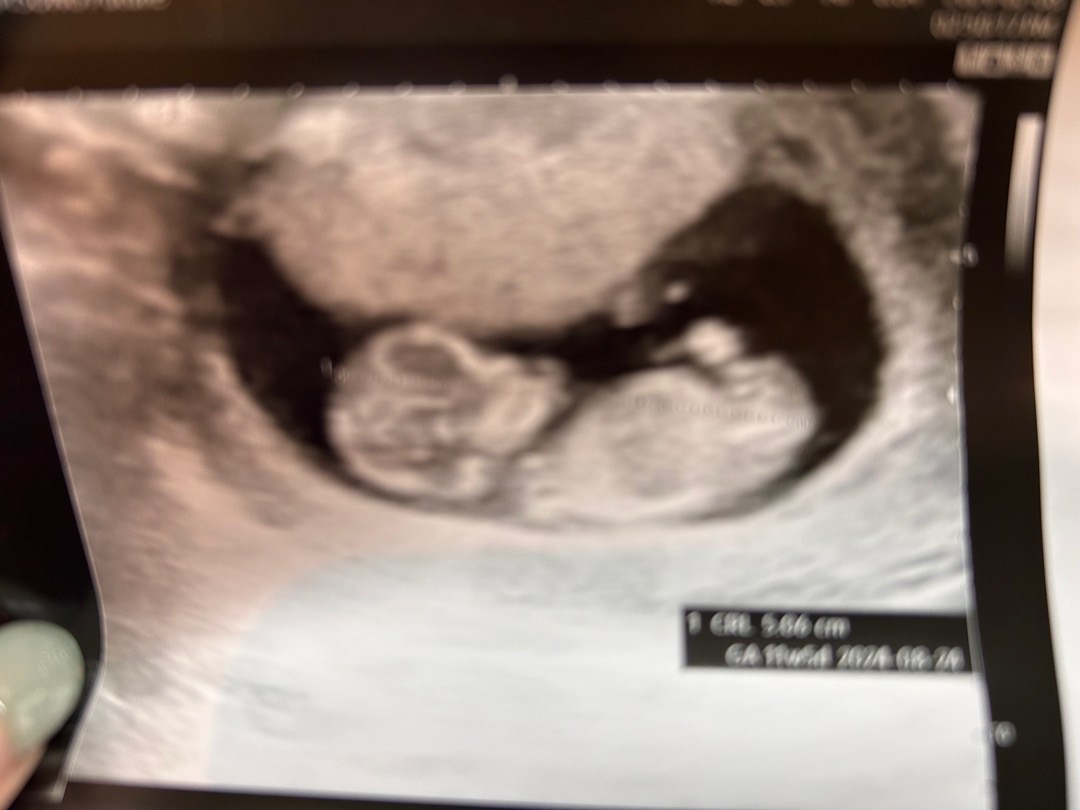

아직은 이르지만 각도법 봐주세요♥️

곧 12주인데 아직 이른 감은 있지만 저도 궁금해서요! 각도법 잘보시는 엄마 아빠 부탁드릴게요👶🏻